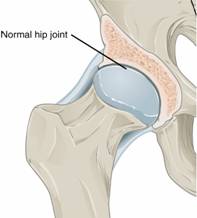

https://upload.wikimedia.org/wikipedia/commons/5/51/X-ray_of_a_normal_hip_joint.jpg

https://commons.wikimedia.org/wiki/File:X-ray_of_a_normal_hip_joint.jpg

Description English: For context, see: en:Hip pain

Description Version 8.25 from the Textbook

OpenStax Anatomy and Physiology

Published May 18, 2016

Date 18 May 2016

Source https://cnx.org/contents/FPtK1zmh@8.25:fEI3C8Ot@10/Preface

Author OpenStax